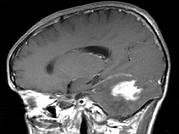

问题 男,41岁,左枕部疼痛,右侧肢体乏力,并渐进性加重半个月,右侧肢体乏力,行走不稳,请根据所提供图像,选择最可能的诊断()

选项 A.(小脑)血管母细胞瘤 B.(小脑)髓母细胞瘤 C.(小脑)炎性肉芽肿 D.(小脑)转移瘤 E.(小脑)星形胶质细胞瘤Ⅰ~Ⅱ级

答案 E